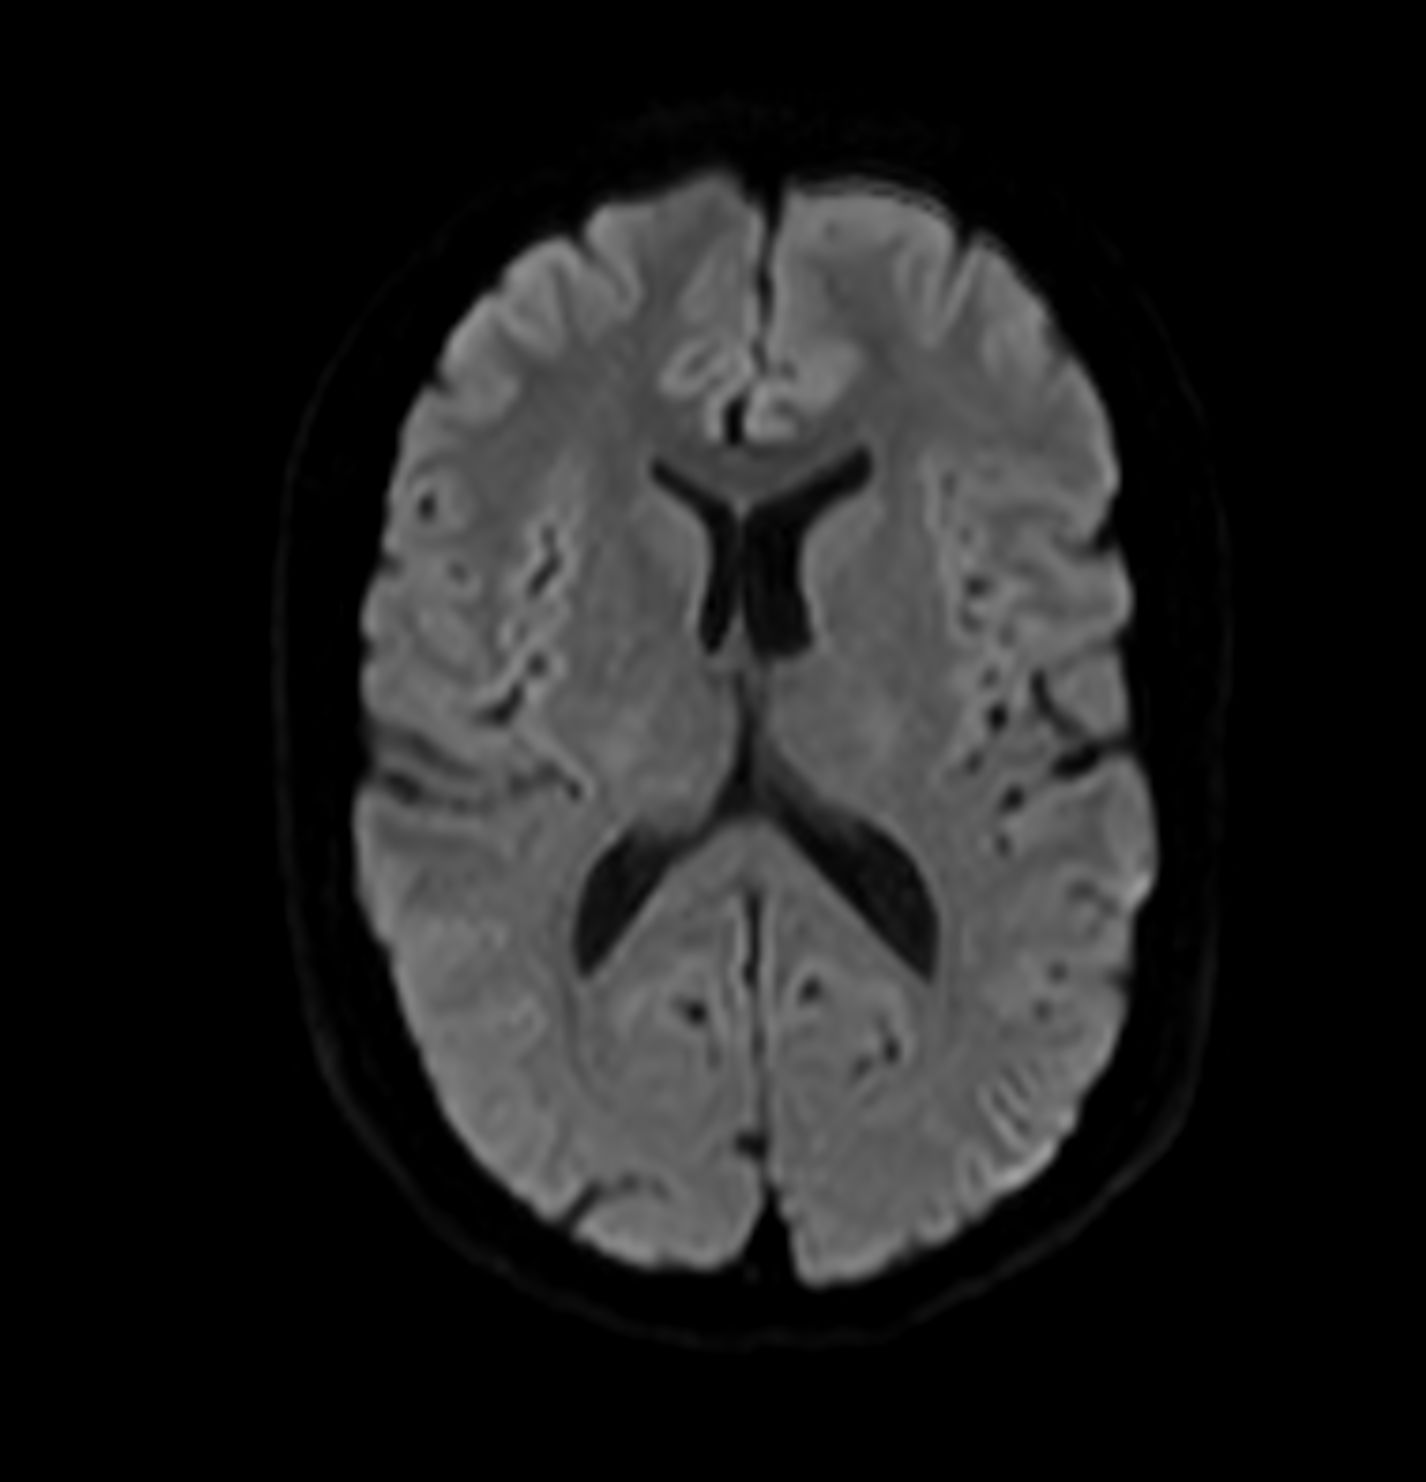

Alzheimer’s Disease Anti-Amyloid Immunotherapies (ARIA) 1.5T

Amyloid clearing medication, such as Aduhelm (Aducanumab) and Leqembi (Lecanemab) have been cleared by the FDA in 2022/2023, to slow down cognitive decline in early-stage Alzheimer’s disease. ASNR-recommendations for AD therapeutic imaging were published in 2022 for eligibility assessment as well as for monitoring for amyloid-related imaging abnormalities. This ExamCard includes ASNR-recommended consensus protocols for imaging of Alzheimer’s Disease Anti-Amyloid Immunotherapies (ARIA). (Cogswell et al., AJNR 2022,43(9)E19-E35;DOI: https://doi.org/10.3174/ajnr.A7586))